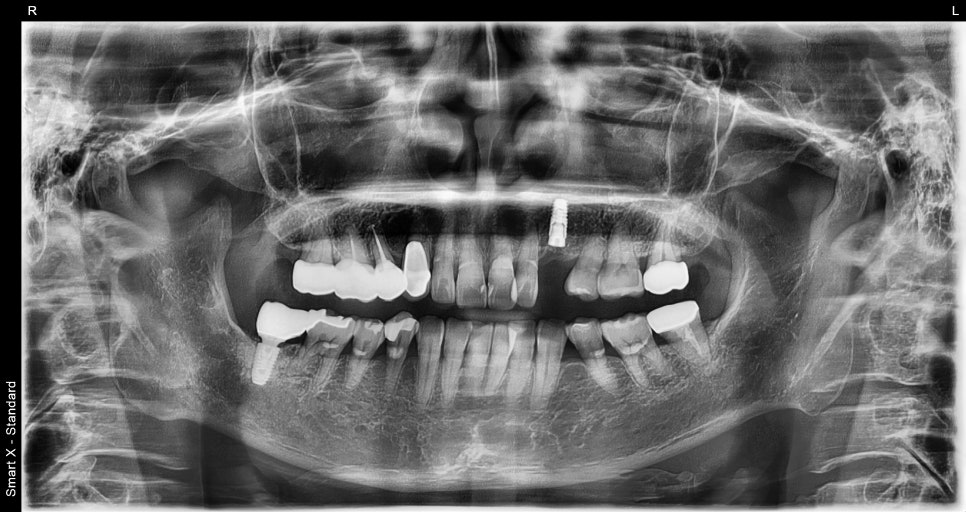

📸 Panoramic X-ray

Initial X-ray of the osteomyelitis patient